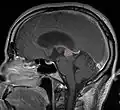

Frequently, paralysis of upward gaze along with several ocular findings such as convergence retraction nystagmus and eyelid retraction also known as Collier's sign and Light Near Dissociation (pupil accommodates but doesn't react to light) are known collectively as Parinaud's syndrome[1] or Dorsal Mid-brain syndrome, are the only physical symptoms seen. This is caused by the compression of the vertical gaze center in the midbrain tectum at the level of the superior colliculus and cranial nerve III. Work-up usually includes Neuro-imaging as seen on the right.